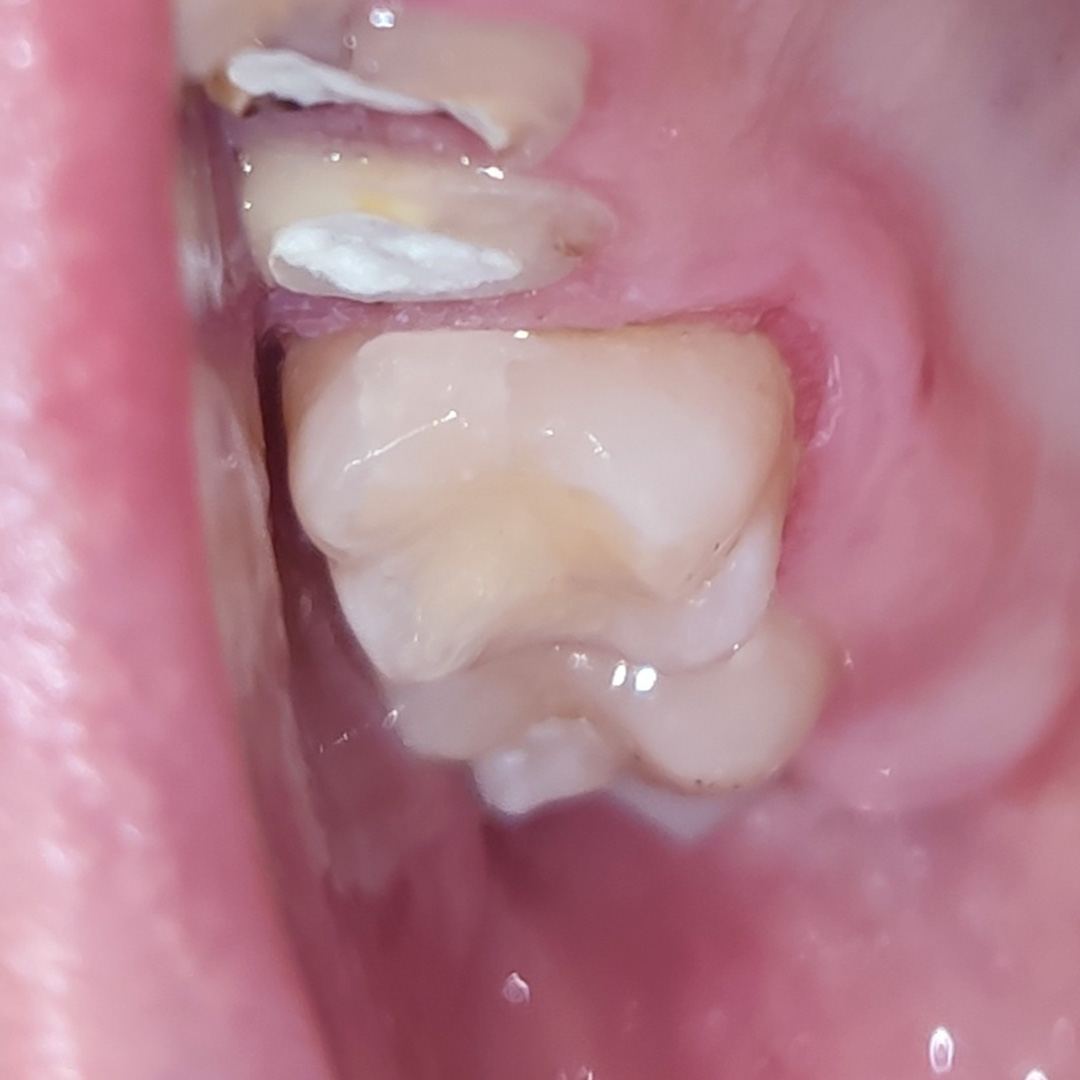

До и после лечения

- поставлена пломба Fuji II

- проведено микроконтурирование и макроконтурирование пломбы